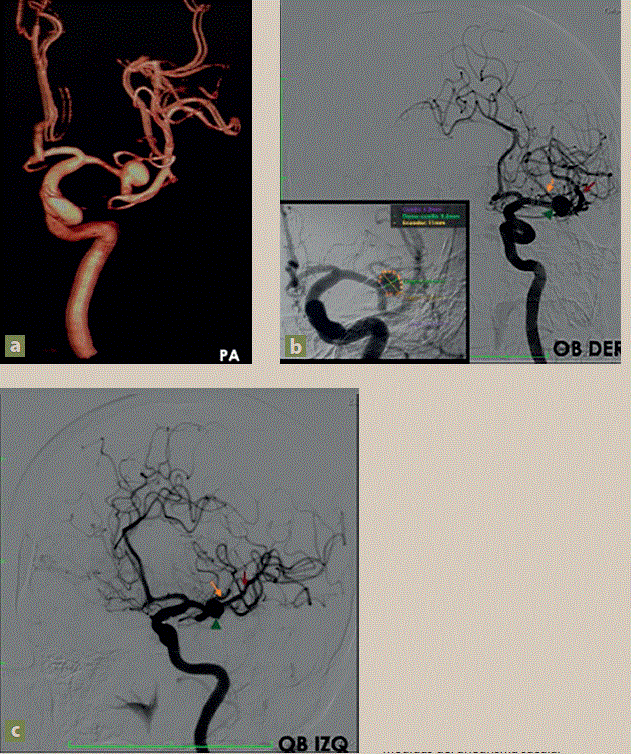

Figura 2 Aneurisma sacular en la bifurcación de la ACMI. a) 3D angiografía diagnóstica (AxDx) en posición posteroanterior, b) y c) AxDx eje carotídeo izquierdo, proyección OBDER-OBIZQ, aneurisma sacular (cabeza de flecha/verde), rama dorsal de la ACMI (flecha naranja), rama ventral (flecha roja). Recuadro: medidas del aneurisma sacular

Los hallazgos descritos muestran imagen aneurismática hacia la bifurcación de la arteria cerebral media izquierda (ACMI), con dimensiones de 6.7× 7.3 mm en sus diámetros (DCX e) y 3.6 mm de cuello, en el cual se observó rama emergente del domo aneurismático.